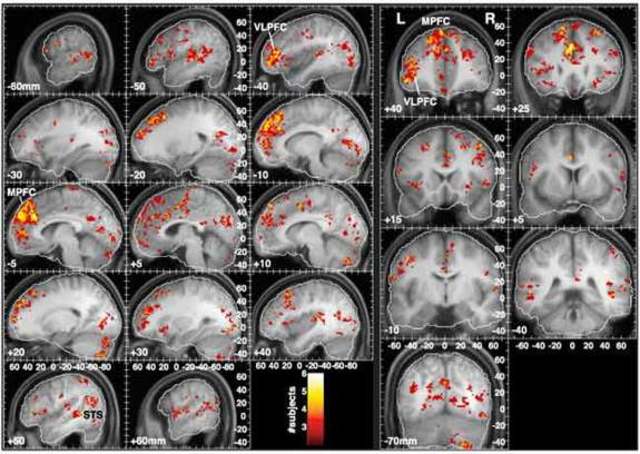

• From Vivaldi to Beatles and Back: Predicting Lateralized Brain Respsones to Music

From Vivaldi to Beatles and Back: Predicting Lateralized Brain Respsones to Music

Alluri, Vinoo. "From Vivaldi to Beatles and Back: Predicting Lateralized Brain Responses to Music." ScienceDirect. NeuroImage, 28 June 2013. Web. 17 Feb. 2015. http://www.sciencedirect.com/science/article/pii/S1053811913007027.